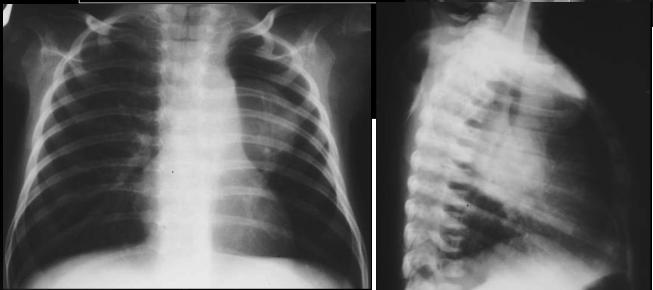

TOGD de estomac en position debout de

face . Image en chaussure de l.estomac . |

Estomac en debout

, profile droit expose |

Estomac en decubitus ventral OAD |

|

Decubitus OAD .

Antre et portion verticale est en pliine de baryte

. Arcade duodenum est bien detecte et en vue

nettement |